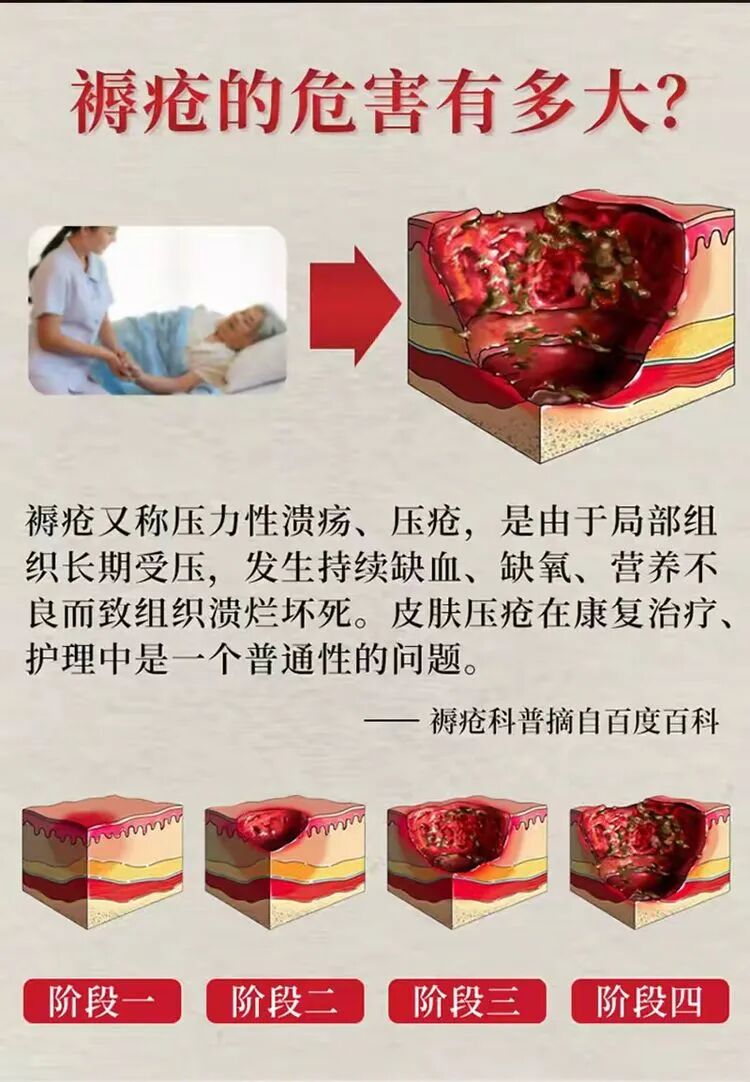

褥疮,又称压疮、压力性溃疡,看似是不起眼的“皮肤破损”,实则是危及生命的隐形杀手——它是机体局部长期受压导致缺血、缺氧,

引发炎症反应,再加上病原菌入侵感染,*终造成的局部组织坏死。更令人揪心的是,褥疮发展速度快到惊人,局部持续受压仅2小时,

就可能引发褥疮;若不及时科学处理,疮面会不断扩大、向深部侵蚀,累及肌肉、骨骼,进而引发败血症、脓毒血症等严重并发症,甚至

致命。据相关文献报道,每年约有6万人死于褥疮合并症,其危害远超常人想象。